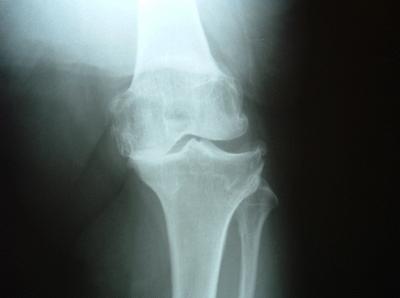

Knee arthritis is a progressive condition in which the cartilage in the knee wears away.  This allows the underlying bones to come into contact, causing pain, swelling, heat, and deformity.  There are several forms of arthritis of the knee because there are three separate compartments that can wear out. Arthritis can involve the patellofemoral joint (between the kneecap and the thigh-bone), the medial tibiofemoral joint (the inside of the knee), the lateral tibiofemoral joint, or any combination.

Arthritis of the knee should first be treated conservatively with anti-inflammatory medications, physical therapy, injections of steroids, injections of hyaluronic acid (Synvisc™, Hyalgan™, Supartz™), or arthroscopic surgery.  Traditional surgery, known as total knee replacement (TKR) replaces all three compartments of the knee.  The latest techniques allow selective replacement of each specific compartment.  This is called uni-compartmental replacement.  Another technique is MIS (minimally invasive surgery) a technique for decreasing post-operative pain and speeding recovery time.